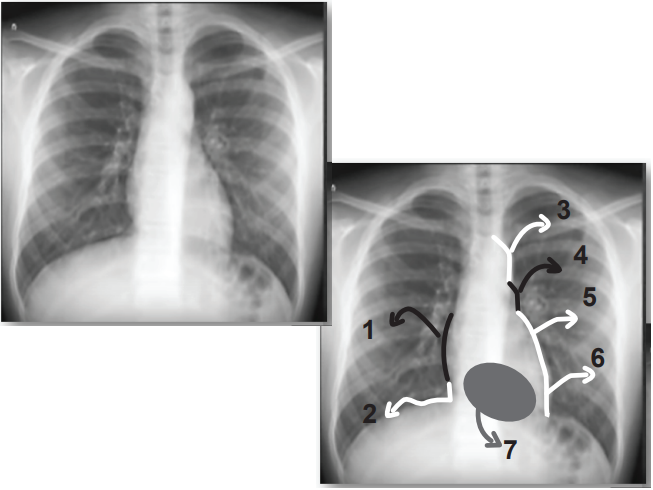

Você preparou uma prova de radiografia de tórax para os seus alunos de biomedicina. Para tanto, escolheu uma radiografia normal de tórax (póstero anterior) de um adulto jovem, e em seguida identificou estruturas de 1 a 7, conforme abaixo, para que o aluno identificasse os contornos da silhueta cardíaca. Seguem as respostas de cinco alunos. Assinale a alternativa do aluno que acertou todas as estruturas:

Questões | |||||||

ALUNOS | 1 | 2 | 3 | 4 | 5 | 6 | 7 |

Mateus | veia cava superior | ventrículo direito | carótida | veia pulmonar | átrio esquerdo | ventrículo esquerdo | ápice do ventrículo esquerdo |

| Lucas | ventrículo direito | ventrículo direito | carótida | aorta | veia pulmonar | ventrículo direito | ápice do ventrículo esquerdo |

| Beth | veia cava inferior | junção com a veia cava inferior | aorta | tronco da veia pulmonar | átrio esquerdo | ventrículo esquerdo | ventrículo direito |

| Julia | átrio direito | junção com a veia cava inferior | aorta | tronco da artéria pulmonar | átrio esquerdo | ventrículo esquerdo | ventrículo direito |

| Daniel | átrio direito | ventrículo direito | carótida | aorta | ventrículo esquerdo | ventrículo esquerdo | ápice do ventrículo esquerdo |